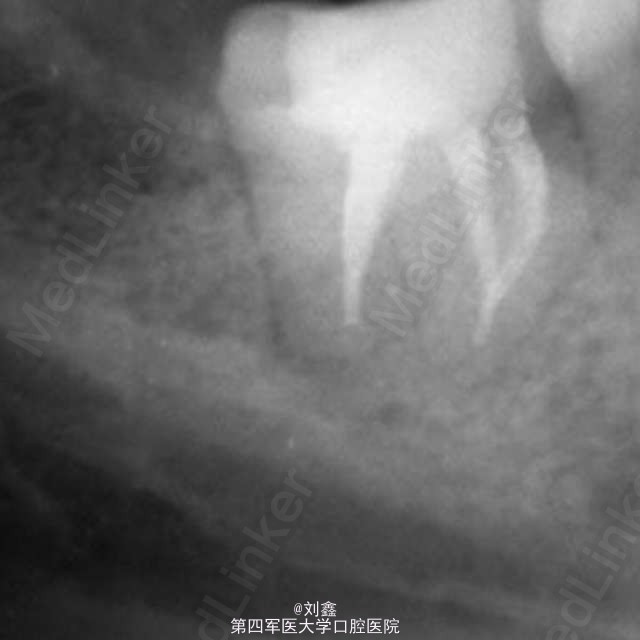

经典病例 根管内断针再治疗

患者女,29,右下后牙3年前于外院行治疗,冲填物脱落来我科。牙片示近中根有断针,遂行再治疗。